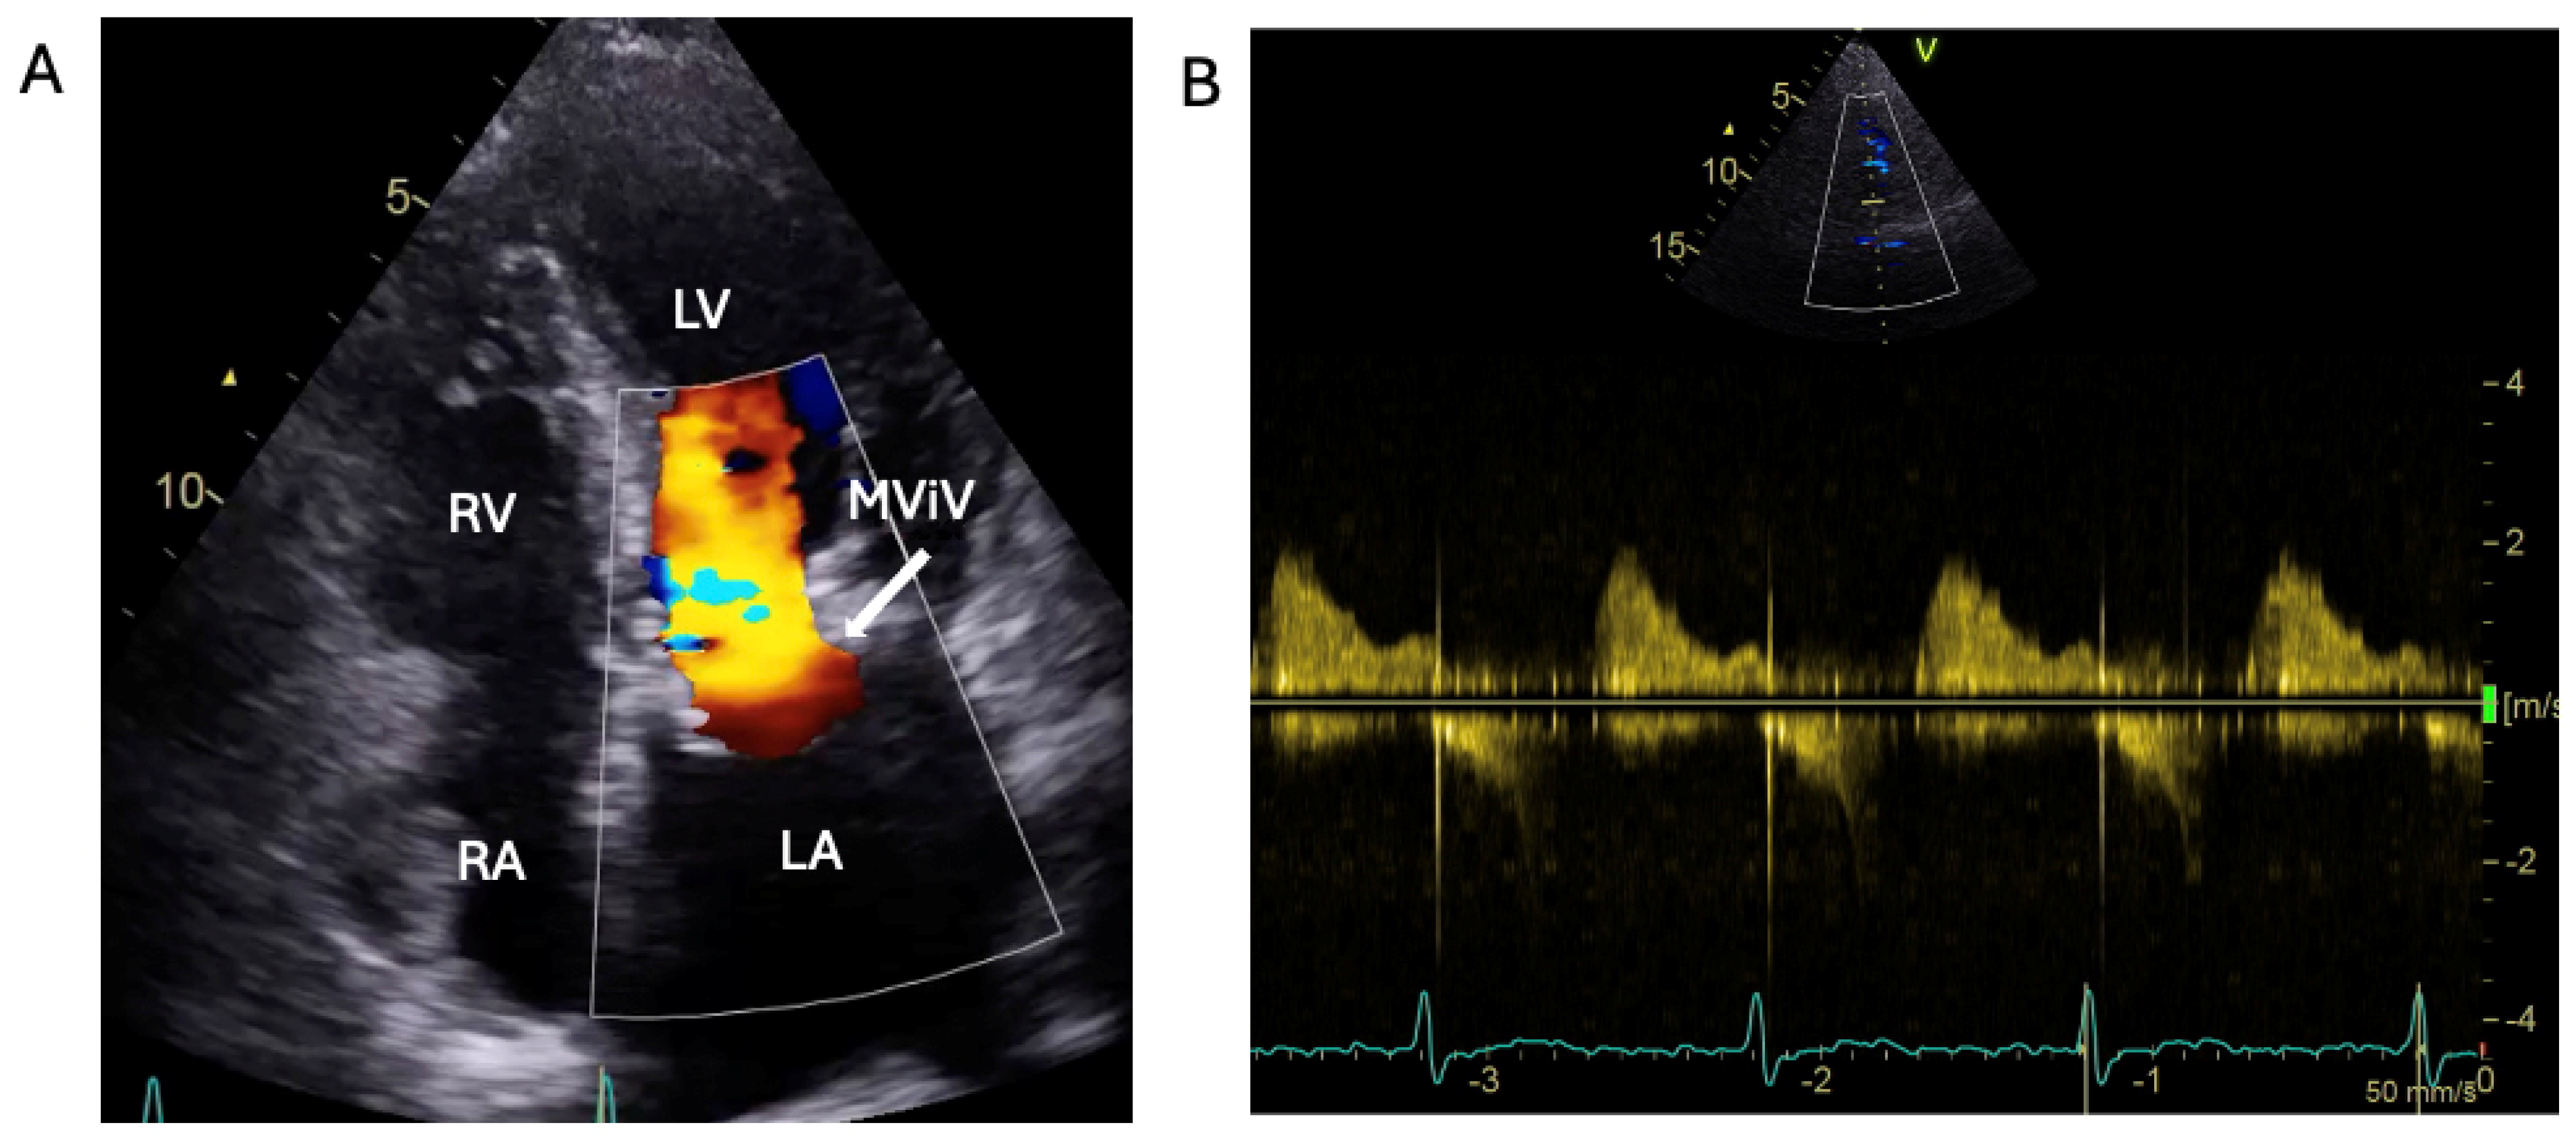

1.1.3. Case 3

2.3. The Saga of Relapsing IE of the Prosthetic Mitral Valve Causing Structural Valve Degeneration and Transcutaneous MViV Prosthesis